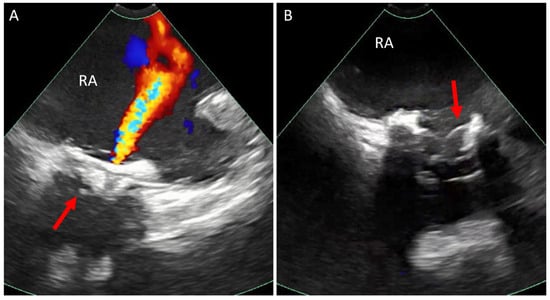

6.1. Baffle Leak Occlusion

- Ehrin, J.; Armstrong, M.D. Intracardiac Echocardiography to Guide Percutaneous Closure of Atrial Baffle Defects. J. Invasive Cardiol. 2012, 24, 473–476. [Google Scholar]

- Kuppahally, S.S.; Litwin, S.E.; Green, L.S.; Ishihara, S.M.; Freedman, R.A.; Michaels, A.D. Utility of Intracardiac Echocardiography for Atrial Baffle Leak Closure in Repaired Transposition of the Great Arteries. Echocardiography 2010, 27, E90–E93. [Google Scholar] [CrossRef]

- Neijenhuis, R.M.L.; Regeer, M.V.; Van der Kley, F.; Vliegen, H.W.; Jongbloed, M.R.M.; Kiès, P.; Schalij, M.J.; Jukema, J.W.; Egorova, A.D. Contemporary Management Strategies of Baffle Leaks in Adults with a Failing Systemic Right Ventricle Late after Atrial Switch: A Case Series and Literature Overview. J. Cardiovasc. Dev. Dis. 2023, 10, 129. [Google Scholar] [CrossRef]